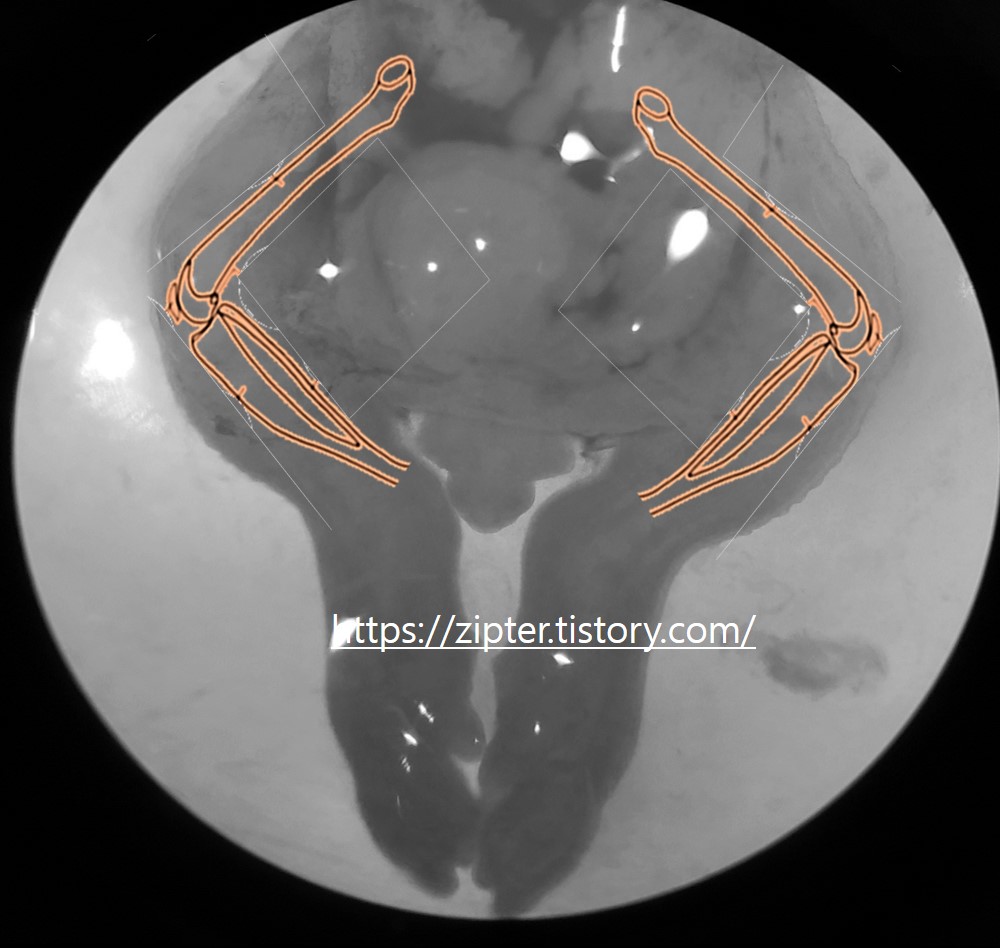

primary chondrocytes culture(연골 세포 배양)

연골세포를 배양하기 위해선 임신 15일차의 쥐에서 배속에 아기가 필요하다. 위 사진처럼 임신 쥐를 머리를 고정시켜준 후 꼬리를 잡아당겨 경추탈골 시켜준 후 1.배속에 아기들을 꺼내고 하반신을 잘라 준다. 2.잘린 하반신을 PSA(4’c)에 담가 둔다. 아래 그림을 보면 우리가 필요한 뼈는 Tibia, 와 Femur이다. 실제로 잘린 하반신을 현미경으로 보면 이렇다. 100파이 dish에 PSA를 넣어 놓고 현미경으로 보면서 작업을 하면 좋다. 3. 하반신의 Forceps으로 닭다리살을 바르듯이 발라 준다. 생각보다 뼈가 물컹하니 조심해서 발라준다. 뼈가 부러져도 상관없으니 천천히 하면 된다. 어느정도 발라 줬으면 아래 사진처럼 나올 것이다. 우리가 배양하는데 필요한 세포들은 저 빨간색 동그라미에 있다. ..